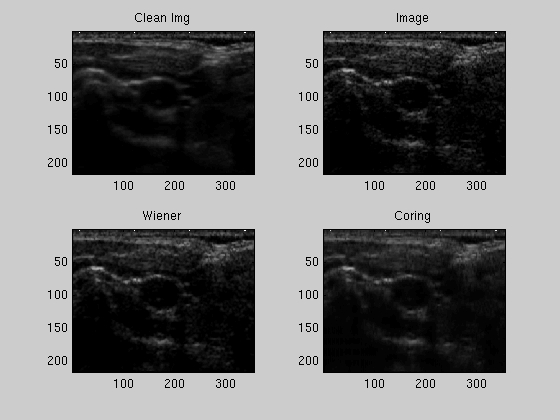

Figure 3a. Image Comparison for Noise Coefficients Modeled as Gaussian

The clean image was obtained by averaging 25 images of the carotid. The test image is shown in the upper-right. The 2 bottom images are the results of denoising using the Wiener filter with a 3x3 block, and denoising using the Bayesian wavelet coring technique, with the noise coefficients modeled as a Gaussian distribution.